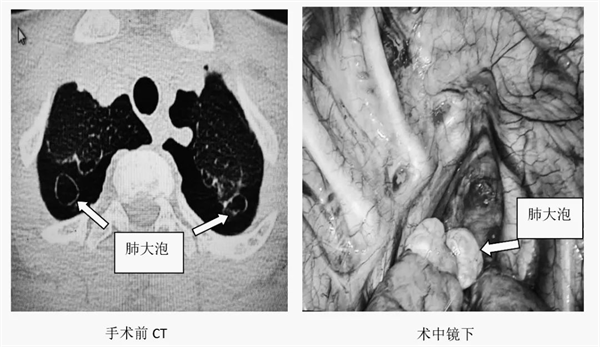

近日,黄陂区人民医院神经外科·胸心外科接诊了一位年仅14岁的患者,该患者突发胸闷胸痛,急诊检查提示双侧自发性气胸,追问病史,已是第二次发作。阅片见患者双肺尖多发肺大疱,经讨论,黄陂区人民医院神经外科·胸心外科团队为患者进行双侧单孔胸腔镜下肺大疱切除术。手术切口仅3-4公分,术后患者恢复良好。

自发性气胸多发于瘦长体型的青少年人群,一般男性多于女性,多见于右侧肺。因为这种身材的人胸腔较长,一旦肺部发育不健全,存在先天性肺大疱,在从事剧烈运动时,会使得肺内压力骤然升高,从而导致肺大疱突然破裂,使空气从肺部进入胸腔,导致自发性气胸。在日常生活中,提拿或高举重量大的物品也容易诱发自发性气胸。青少年如果一旦出现胸闷、胸痛、呼吸困难等症状,应立即就医,以免延误病情。黄陂区人民医院神经外科·胸心外科希望能提高公众对自发性气胸的认识与重视程度,为青少年的健康成长保驾护航。